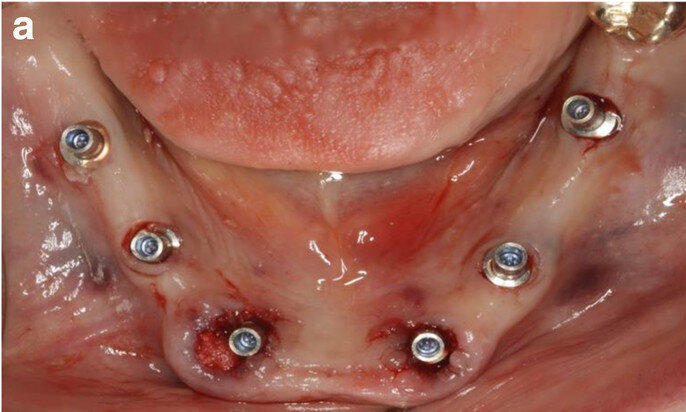

Fig. 9a: Occlusal views of the abutments (a) and of the immediate provisional restoration that were passively bonded in situ (b).

Fig. 9b: Occlusal views of the abutments (a) and of the immediate provisional restoration that were passively bonded in situ (b).

After removal of the second surgical template, the standard titanium abutments were mounted on to the implants at a torque of 15 Ncm (Fig. 9a). The gaps between the abutments and the FDP were filled with a dual-curing composite material and the screw-retained immediate provisional FDP delivered. The occlusion required only minor adaptations owing to the accurate digital preoperative planning (Fig. 9b). The postoperative panoramic radiograph showed the parallel axes of the six implants (Fig. 10).